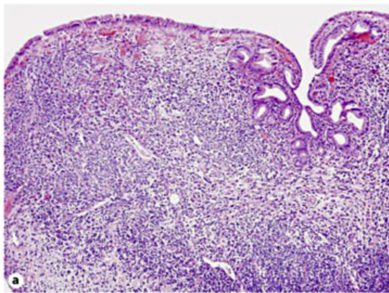

- 病理では、好酸球の浸潤、small- to medium サイズの壊死性血管炎が報告されている

- 好酸球を伴わないmonocyteの浸潤を認めた例も報告されている